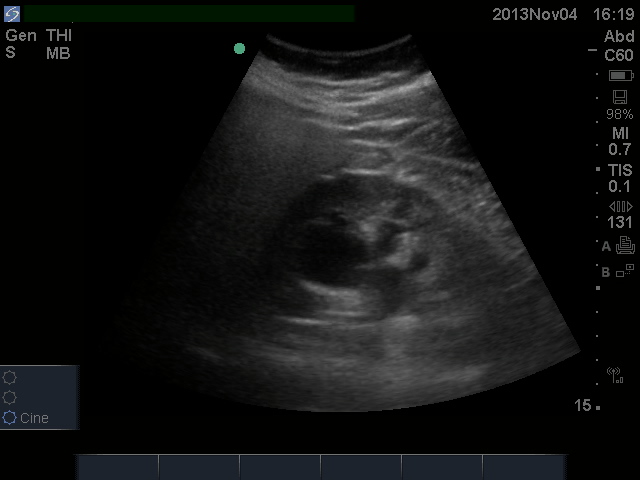

Does this patient have hydronephrosis

The primary question for renal POCUS is that of hydronephrosis.  It’s presence strongly points towards renal colic as the diagnosis in the appropriate patient.  2 minute video here.